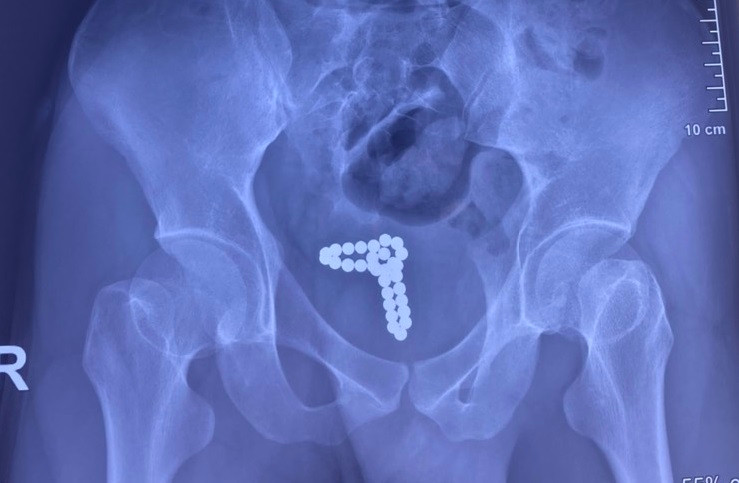

| Kết quả kiểm tra hình ảnh cho thấy, chuỗi bi kim loại nằm trong bàng quang của bệnh nhân |

Tại Đơn vị Nam khoa, qua thăm khám lâm sàng và làm các xét nghiệm, chụp X-quang bụng, các bác sĩ xác định dị vật là chuỗi hạt kim loại có từ tính dính với nhau thành chuỗi đang nằm trong bàng quang của người bệnh. Dị vật gây tổn thương bàng quang là nguyên nhân khiến bệnh nhân tiểu ra máu.